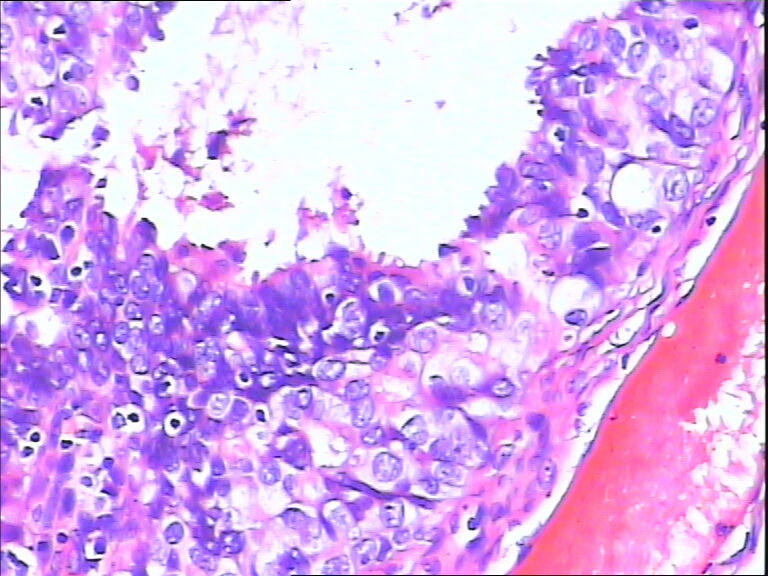

女,43y

左输卵管积液

输卵管长4.5cm;直径:0.8cm

输卵管增生性上皮病变。

慢性炎伴上皮增生

良性,炎症改变

考虑炎症